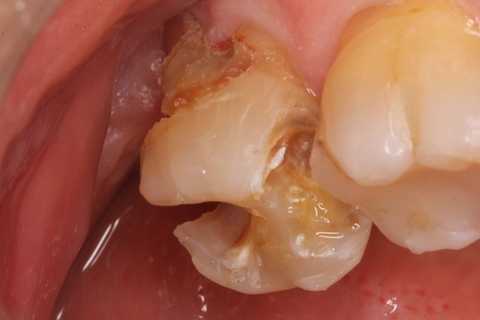

30代女性、左下7、Per、動揺度2.5

今日の症例は8年前に僕が親知らずが遠心に食い込んで虫歯になったものを神経を取らずにCR充填したものだが、とうとう接着剥がれが起こり神経が死んでしまった。神経は全く残っておらず。溶けてなくなっていた。

レントゲン写真では炎症は歯根周囲の歯槽骨に及んでいる。

他院で抜歯しかないと言われたそうで、仕方なく当院に来られた。

この症例は歯根内部をいじられていないので、根管治療は難しくない。CRで歯冠を再建するのが難しかった。